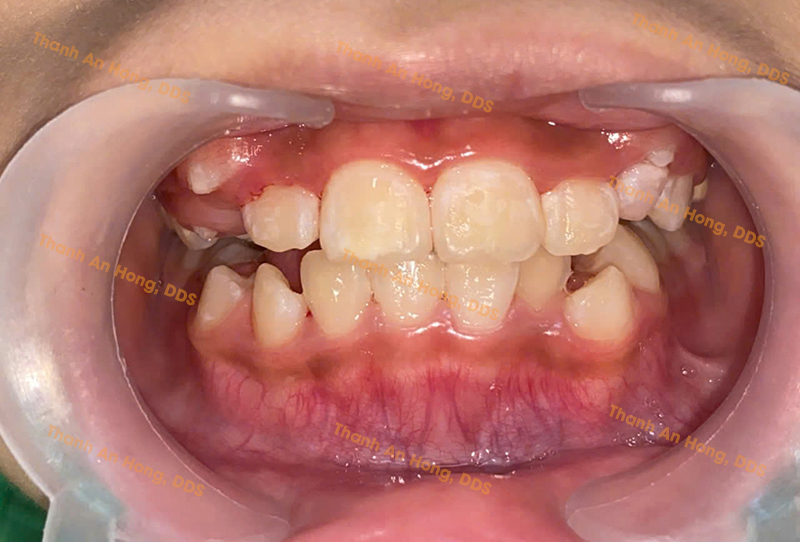

HÌNH ẢNH THỰC TẾ

Chỉnh cắn ngược